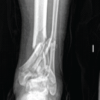

Case Report: A 25 year old male presented to orthopaedic causality with injury to right ankle following a road traffic accident. Patient complained of severe pain and deformity of ankle following injury. On examination ankle was deformed and swollen. Plain radiographs of right ankle joint revealed total anterolateral dislocation of talus without any accompanying ankle fracture. CT scan with 3D reconstruction also confirmed our radiographic findings. Under spinal anaesthesia and fluoroscopic guidance closed reduction was performed. To maintain reduction a 3mm K-wire was passed from calcaneum to tibia through talus. A posterior below knee splint was applied. Patient was followed every three months till one year. At one year follow up patient had good range of motion at ankle and subtalar joint.